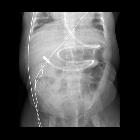

Infant after

feeding tube placementAXR shows a feeding tube coursing along the greater curvature of the stomach and then passing through the pylorus and duodenum with the tip in the proximal jejunum. A nasogastric tube is also present with its tip within the body of the stomach.The diagnosis was appropriate position of the feeding tube tip.